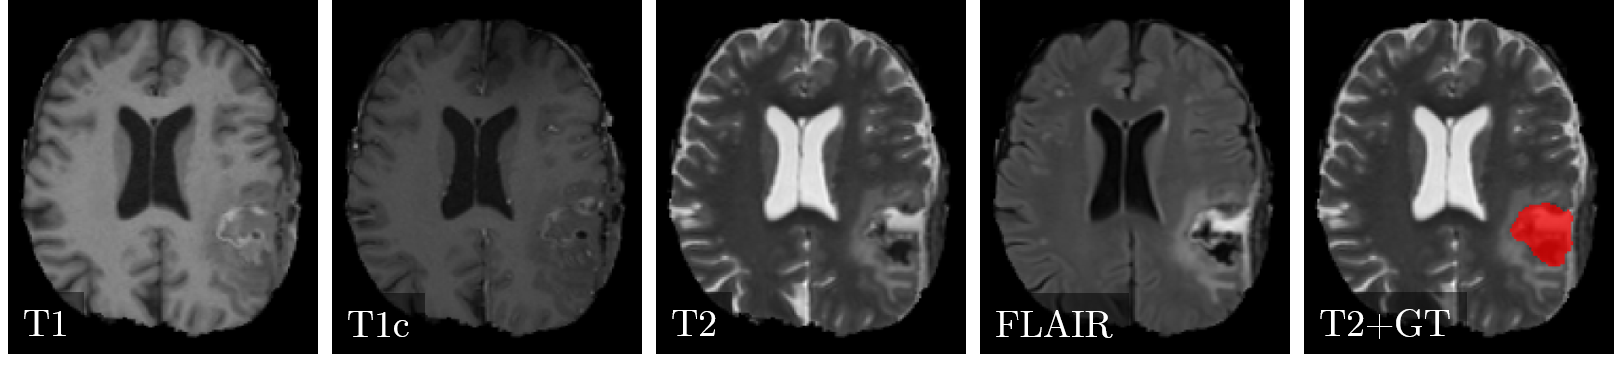

Postoperative magnetic resonance images with 30 subjects to evaluate the post-operative (i.e., after tumor resection) status of glioblastoma patients are available. The images were acquired in the four standard sequences (T1-weighted (T1), T1-weighted post-contrast (T1c), T2-weighted (T2), and Fluid-attenuated inversion-recovery (FLAIR)). All sequences of a subject are co-registered and anonymized, i.e., skull-stripped. Three clinical radiation oncology experts with different levels of expertise (two years, four years, and over six years of clinical experience) created the label maps. These maps delineate the cavity after tumor resection and are used for radiotherapy planning. The difficulty of the task is associated with the presence of blood products, cerebrospinal fluid infiltration and air pockets, which change the appearance of the resection cavity. The dataset ground truth was created by a majority voting of the three expert segmentation. Figure 1 illustrates the four sequences and the ground truth in the dataset on an exemplary image slice.

Refer to caption

Figure 1: Example case of the postoperative brain tumor dataset. From left to right the images correspond to the four sequences T1-weighted (T1), T1-weighted post-contrast (T1c), T2-weighted and Fluid-attenuated inversion-recovery (FLAIR). The image on the right shows the ground truth (GT) as an overlay on the T2 image.